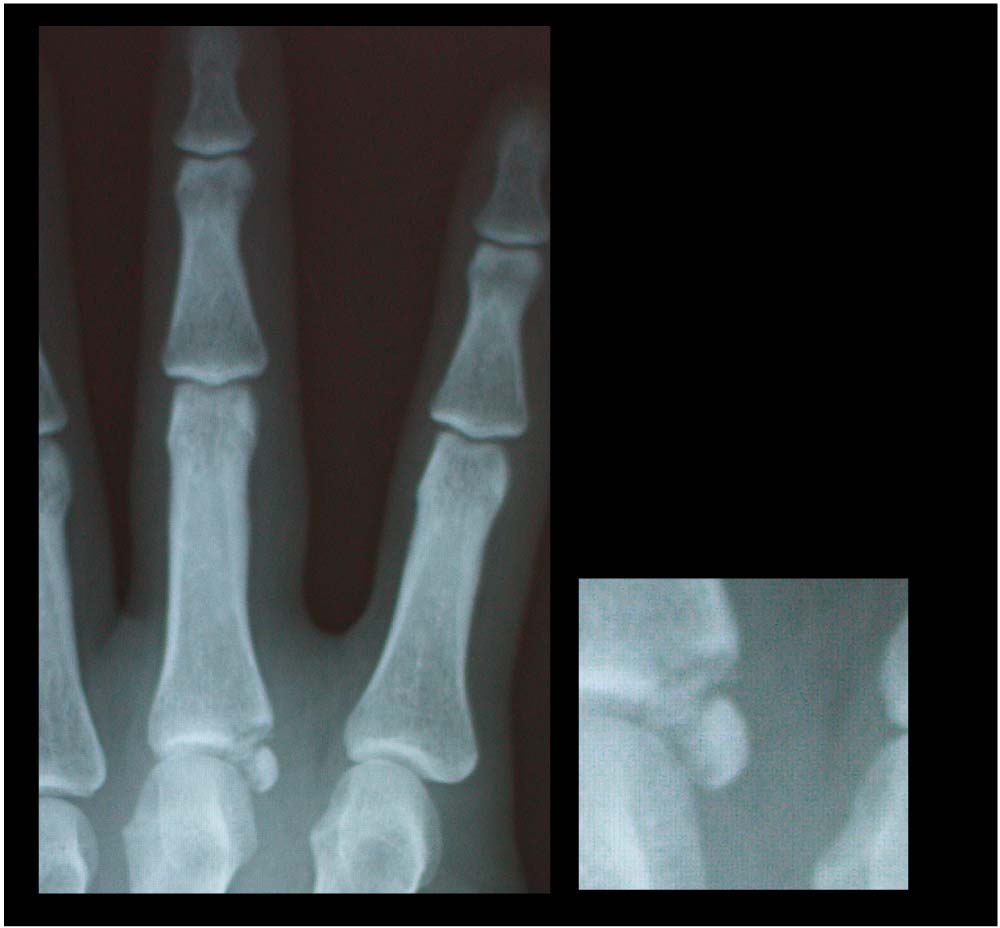

先日、地元のparkのフラットで、寒いからUPを しっかりやってたら、指から地面について指をグリッチョしてしまいました。。 グリッチョした時にポキッ??コキッ??とゆうような 音がしたんですが、指も動くので、大ジョブっしょと 思ってたんですが。。。どんどん腫れてきて。。 次の日の仕事は、左手、あまり使えなく。風邪もなおってないので、早退して病院へ

見事とは、いいづらいような微妙な。。わかりづらいので拡大!!

他の指と比べると何やら、丸い石ころのような物が。

これが 原因の骨が欠けたみたいな。。

なんちゃら骨折って言ってました。

これ、ほっといても 治るらしいんですが、この石ころみたいなのが肉の中で回転してる らしく

ほっといて、うまくつくかわからなく後遺症みたいになる可能性もあるかもと。。。言われたので来週から手術&入院してきます。。。

だいぶ昔しに鬼グリッチョした時の写真。。。

靭帯伸ばしてこの先2ヶ月ギプスするハメになる前の状態。。